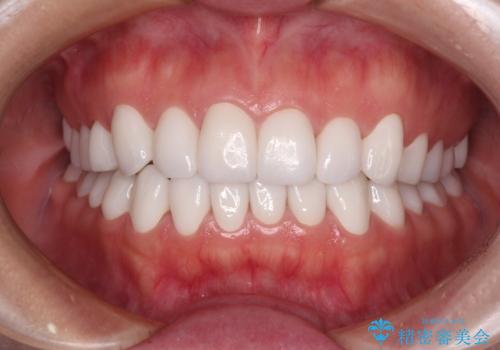

- 奥歯の銀歯をセラミックにしたいとのことで来院された患者様です。

当初は奥歯のみの治療をご希望でしたが、話を進めていくうちに、軽度ではあるものの、幼少期の薬の影響で歯が変色していることがコンプレックスであるということが分かりました。

長年歯の色が塞ぎ込んでいた部分があるとのことで、これを機会に全ての歯を真っ白にするために、オールセラミッククラウンにて補綴治療を行うこととしました。

より白さが目立つように、自然な仕上がりではなく、作り物の雰囲気があるフルジルコニアクラウンにて補綴治療を行いました。